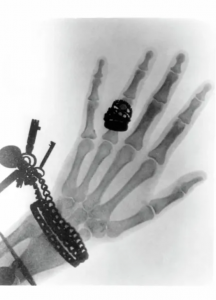

В 1895 году немецкий физик Вильгельм Конрад Рёнтген открыл рентгеновское излучение. Первым изображением, полученным с его помощью, стала кисть руки его жены с кольцом. Вот эта фотография:

Когда об открытии стало известно, как вы думаете, что именно произошло дальше? Правильно, мир столкнулся с эффектом, который сегодня назвали бы технологическим хайпом.